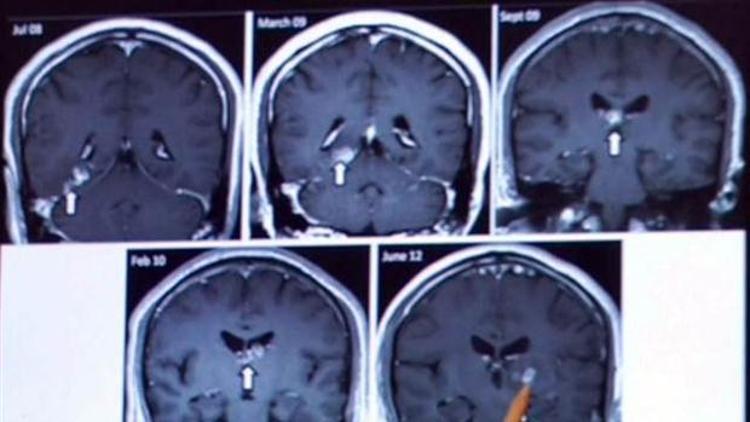

Tenyayı inceleyen Cambridge Sanger Enstitüsü bilim adamları parazitin hastanın Asya gezisinde çiğ olarak yediği kurbağa etinden gelmiş olabileceğini açıkladı. Cambridge Sanger Enstitüsü görevlisi bilim adamı Neuropatalog Andrew Dean, önce baş dönmesi ve kramp şikayeti ile hastaneye başvuran hastada tenyanın tesadüf olarak bulunduğunu söyledi. Focus dergisinin haberine göre, adamın beyninde dört yıl boyunca büyüyen ’Spirometra erinacei europaei’ tipi tenyanın, İngiltere’de ilk kez ortaya çıktığı belirtildi.

Ameliyat sonrası sıhhatine kavuşan ve adı açıklanmayan ingiliz’in Cambridge Üniversitesi Kliniği’nden taburcu olduğu belirtildi. "Spirometra erinacei europaei" tipi tenyalar, genelde Akdeniz Bölgesi ve Doğu Asya’da bulunuyor. 75 santimetreye kadar büyüyebilen bu tenyalar, 8 milimetre kalınlığa ulaşabiliyor.